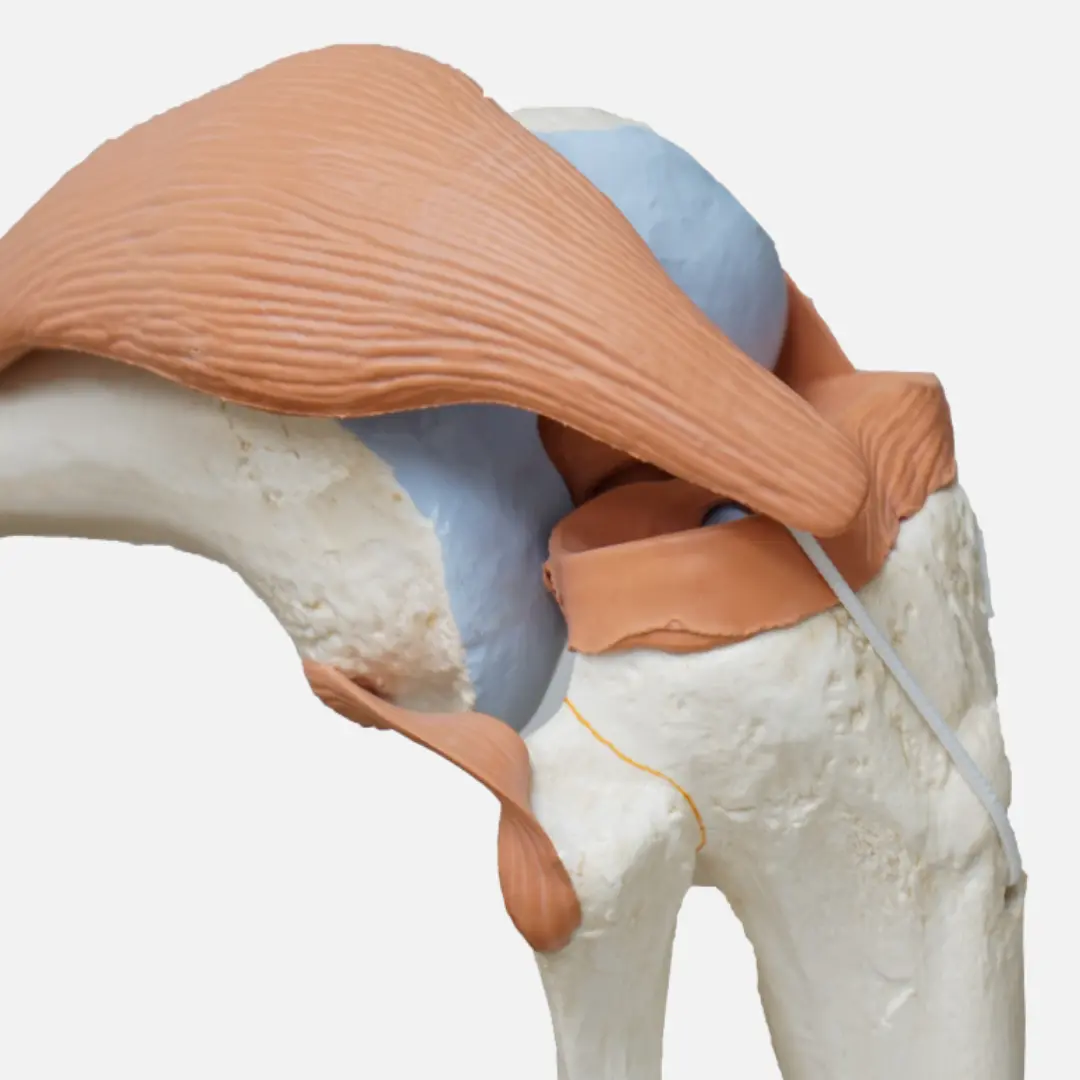

퇴행성 관절염은 가장 흔한 관절염으로, 주로 관절 연골의 손상으로 인해 발생해요. 초기증상은 연골이 닳기 시작하면서 나타난답니다.

- 자가면역 반응: 면역 체계가 관절을 감싸는 활막(synovial membrane)을 공격하여 염증을 유발하는 것이 근본적인 원인이에요. 활막은 관절액을 생성하여 관절을 윤활하는 역할을 하는데, 여기에 염증이 생기면 관절이 붓고 통증을 유발한답니다.